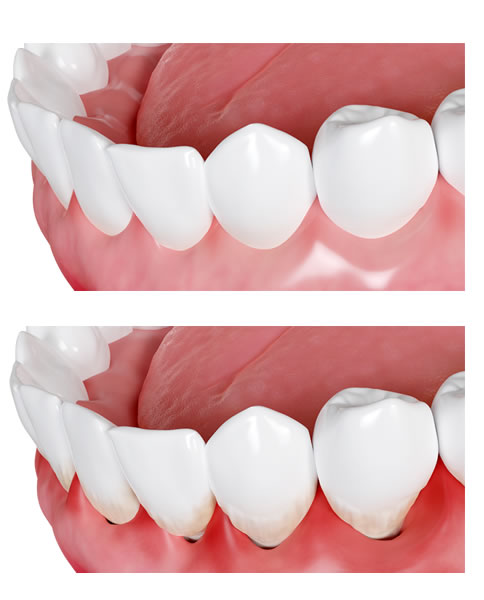

Los tratamientos de conducto vuelven al diente más vulnerable por la pérdida de estructura dental, acceso a nutrientes (la pulpa era el tejido blando que suplía al diente de un flujo sanguíneo y con ello nutrientes, agua y minerales) y elasticidad (la pulpa suplía al diente con fuerzas uniformes de soporte y elasticidad), volviéndolo más propenso a fragmentarse, lesionarse y caerse.

Debido a esto, se realizan restauraciones, como las coronas dentales, capaces de brindar una capa protectora al diente, que lo aísle parcialmente de las fuerzas externas que lo deterioran.